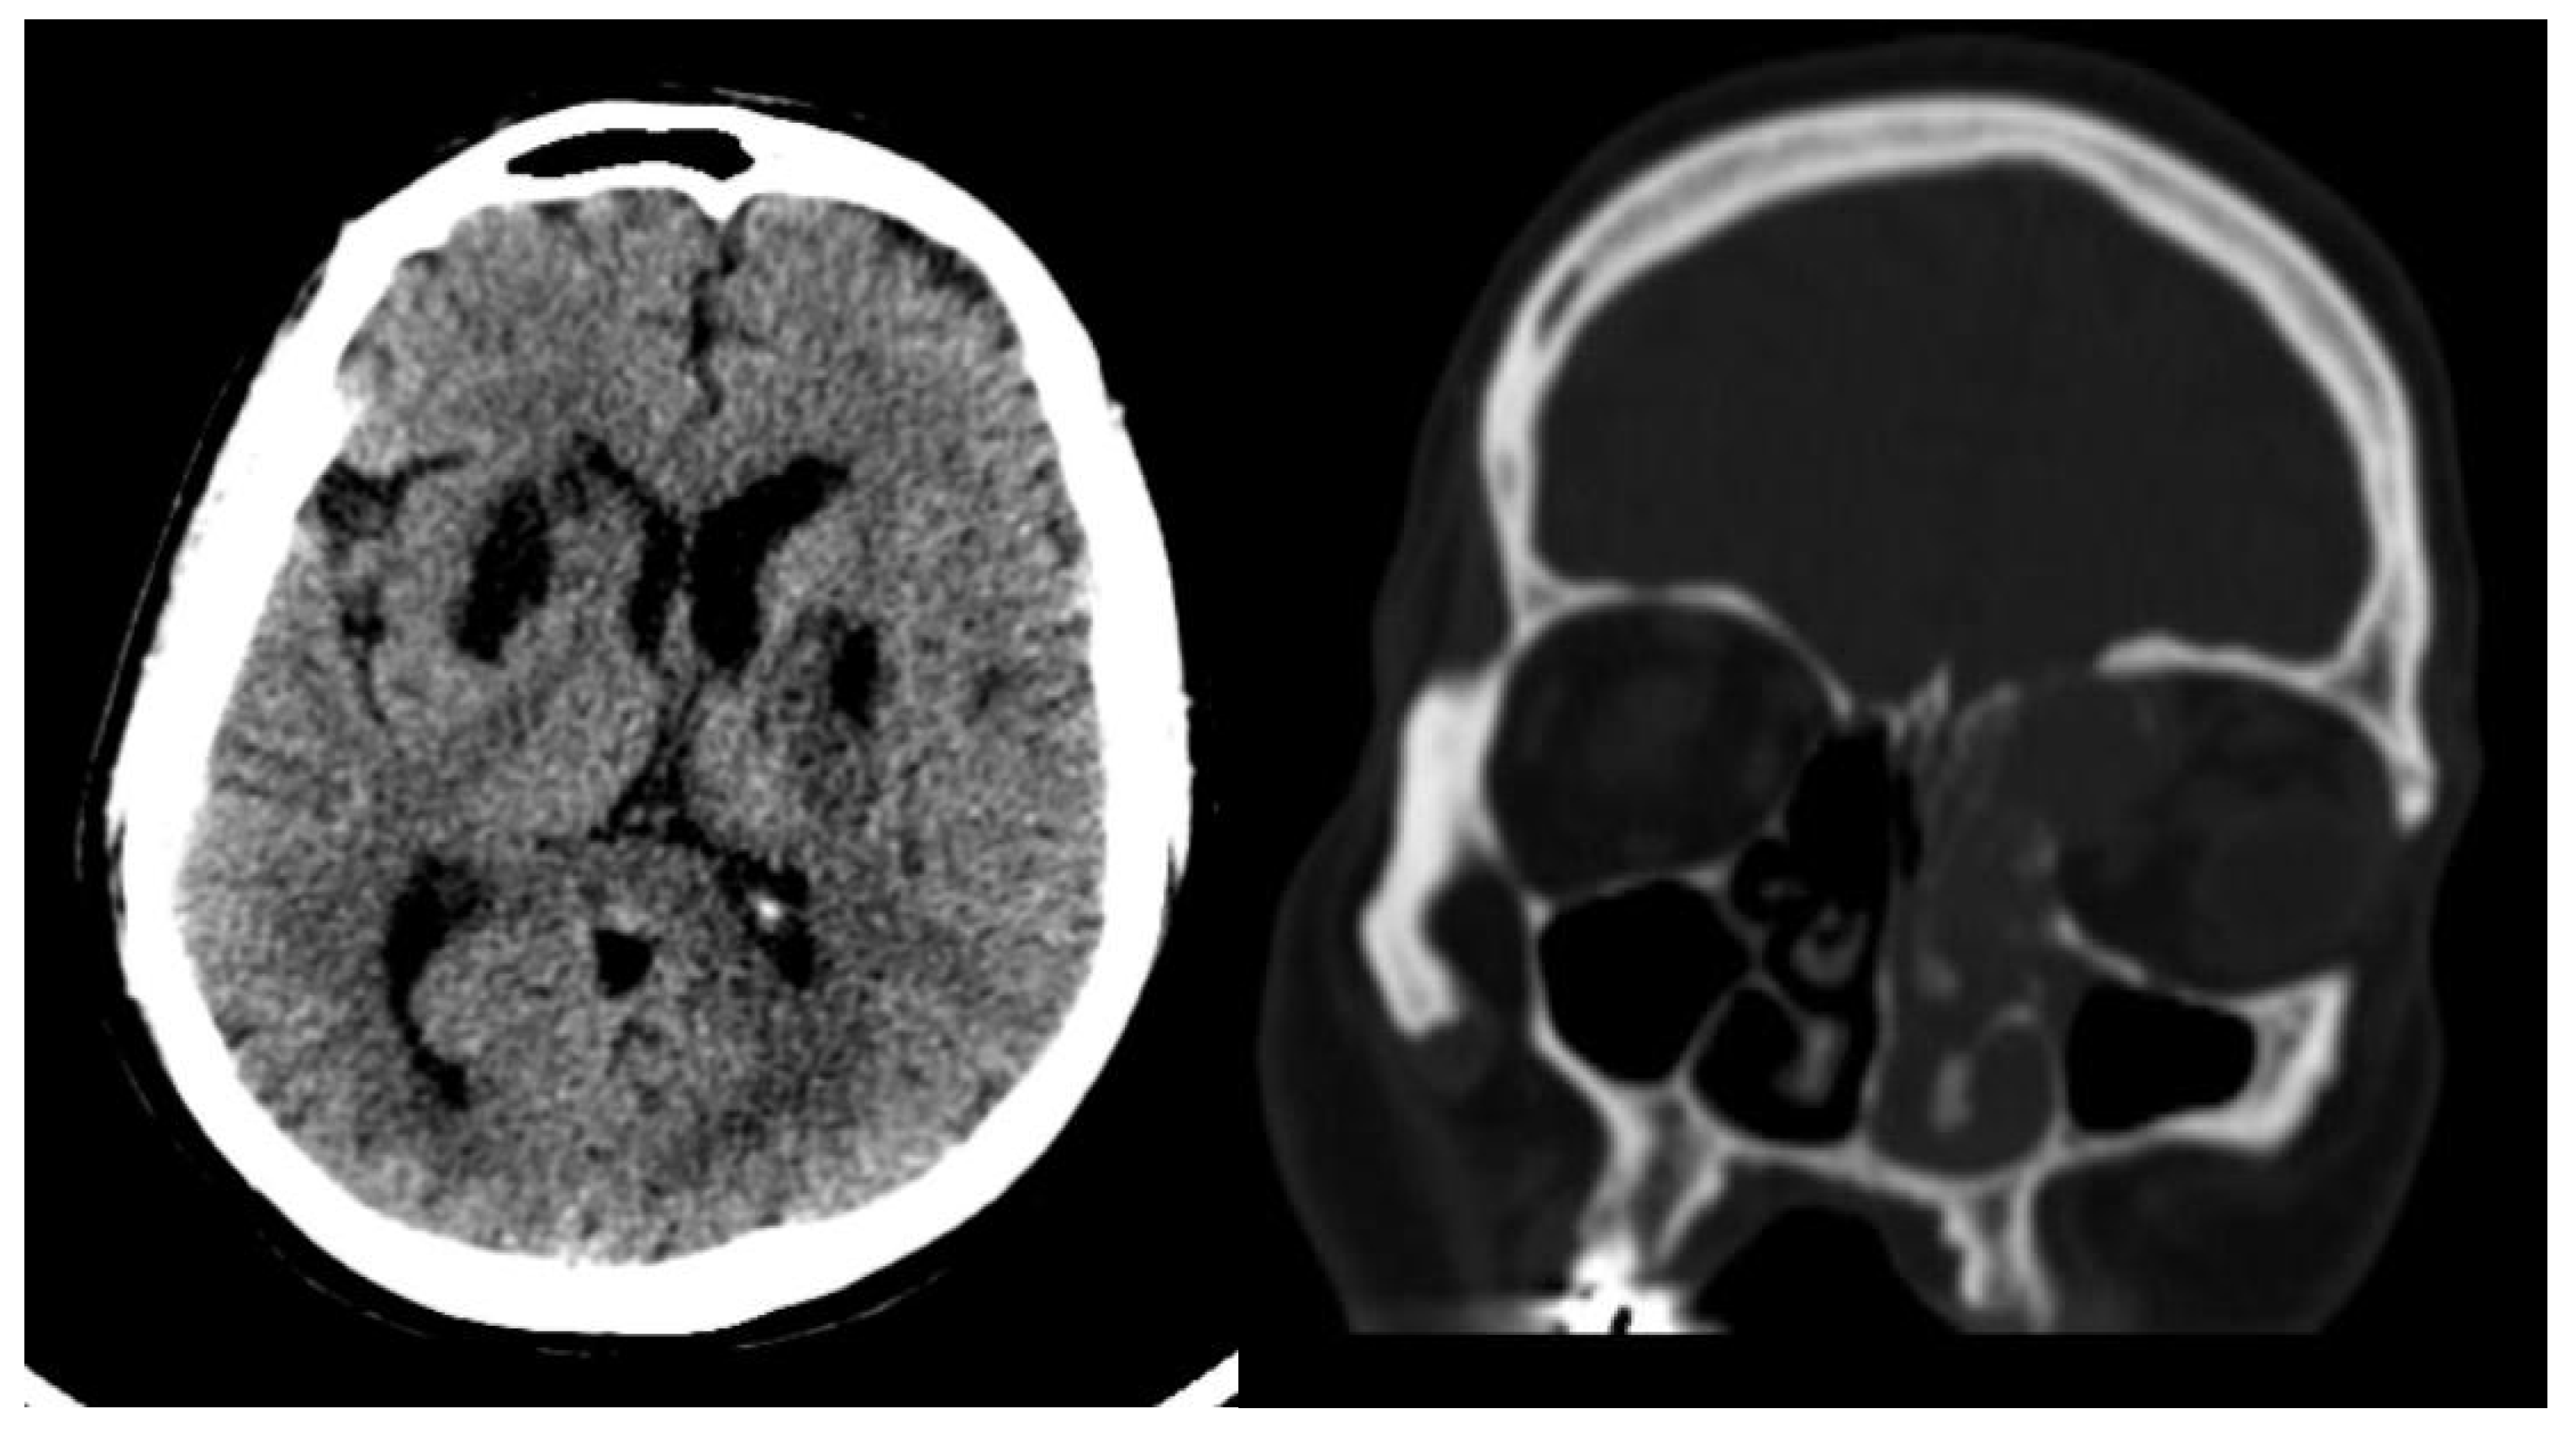

Radiological findings from high-resolution computed tomography (CT) (Figure 1) revealed bilateral basal ganglia hypodense areas suggestive of chronic ischemia and a more lateral hypodense area toward the left basal ganglia indicative of subacute ischemia. A coronal cut showed an iso-dense expansible soft tissue lesion with internal foci of calcifications centered in the anterior aspect of the left ethmoid sinus with protrusion to the left orbital conus, pushing the medial rectus muscle laterally with complete obliteration of the left frontal sinus. Brain magnetic resonance imaging with Fluid-attenuated inversion recovery sequence (MRI FLAIR) (Figure 2) showed an abnormal hyperintense signal in the left cavernous sinus and a left ethmoidal sinus synovial tumor.

Figure 2. Brain MRI DWI sequence showing abnormal hyper-intense signal (bright) in the distribution of the left cavernous sinus. The left ethmoidal sinus synovial tumor is also noted.